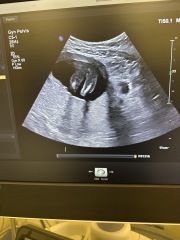

Any guess ?

Girl or boy